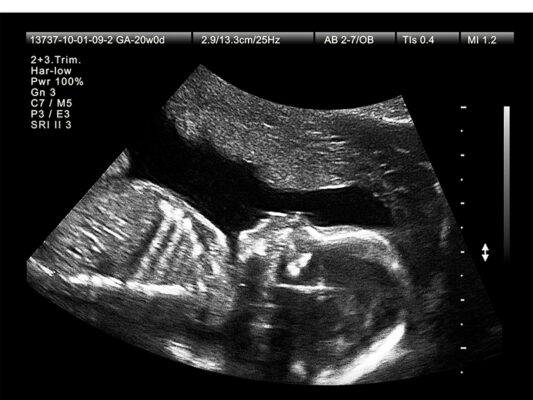

A. Siêu âm 2D

Siêu âm 2D là loại phổ biến nhất của siêu âm thai. Nó cho phép tạo ra hình ảnh 2 chiều của thai nhi và giúp bác sĩ xác định kích thước của thai nhi và vị trí của nó trong tử cung.

Hình ảnh kết quả siêu âm 2D